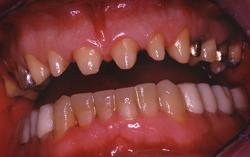

Couronnes tout céramique. Présentation d’un cas clinique : Patient d'une quarantaine d'année bruxomane, présentant des douleurs cervicales et des céphalées matinales. Il existe aussi une perte de la dimension verticale d'occlusion.

Présentation d’un cas clinique :

Patient d'une quarantaine d'année bruxomane, présentant des douleurs cervicales et des céphalées matinales.

Il existe aussi une perte de la dimension verticale d'occlusion.

Absence de visibilité des dents supérieures lors du sourire forcé

Vue intra-buccale en occlusion

L'espace de repos est très important. La lèvre supérieure est tombante

Avant.

Après avec augmentation de la DVO de 6 mm.